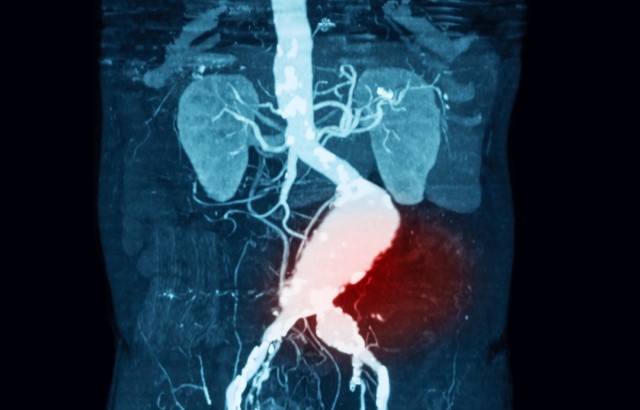

An abdominal aortic aneurysm is a balloon-like swelling in the abdominal section of the aorta, which carries blood away from the heart and around the body.

There are currently no treatments that can stop an aneurysm developing or growing. If an AAA becomes too large, it can burst causing massive internal bleeding.